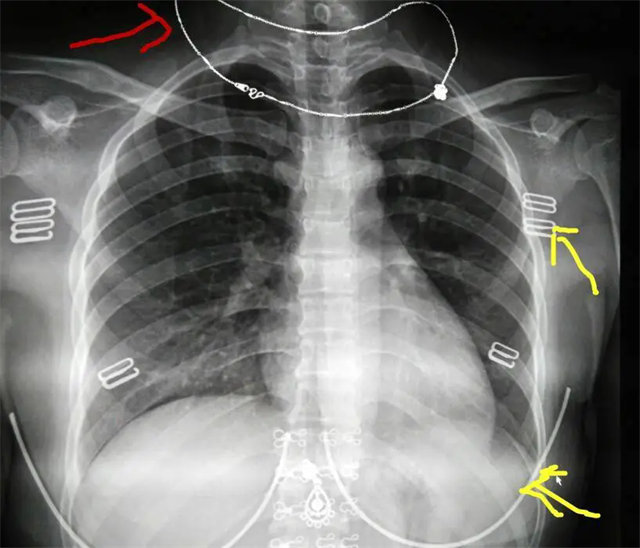

拍攝的不合格胸片的缺陷和解決方法

缺陷:肩胛骨未完全拉離肺野,吸氣不完全,存在金屬偽影遮擋,略有聳肩,且肺尖顯示不好,圖像顆粒感較強(qiáng),管電流量不夠,信噪比偏低。

解決:去除金屬物品后,按標(biāo)準(zhǔn)體位,使患者雙肩旋前與前胸一并緊貼成像件,適當(dāng)調(diào)高mAs,然后深吸氣后屏氣曝光。